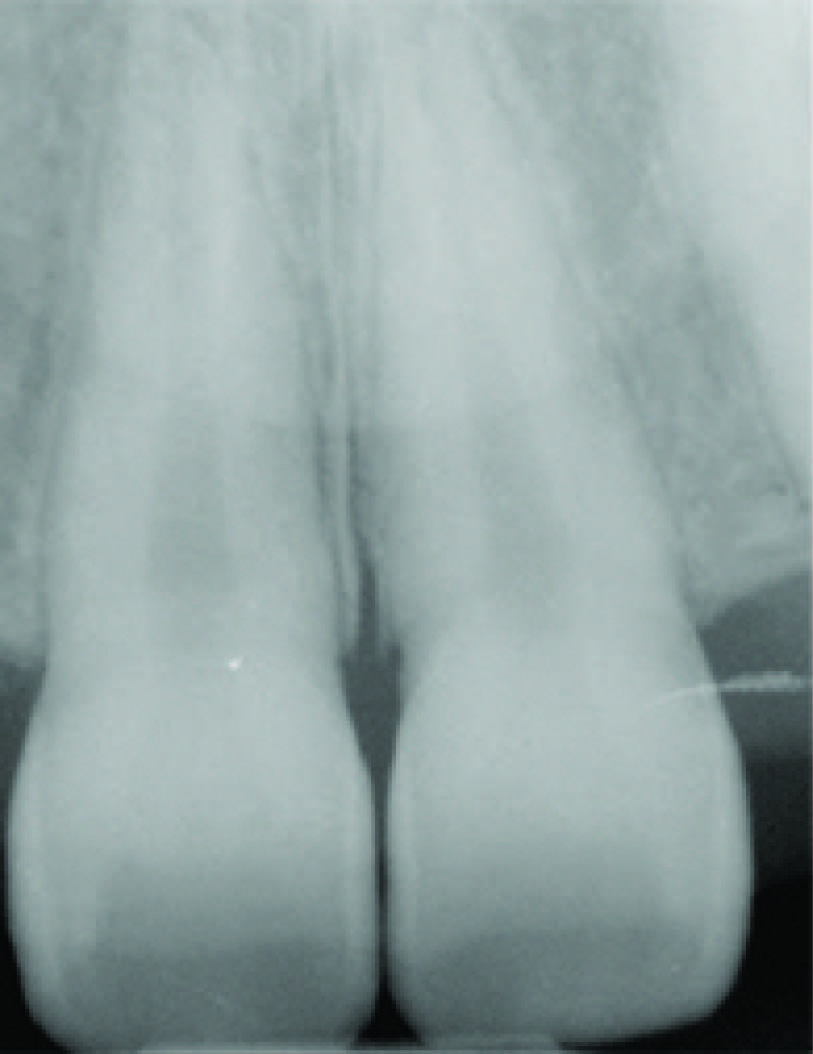

Intra-oral periapical radiograph of 11, 13 and 21 revealed enlarged pulp chambers and root canals [Table/Fig-4]. Patient was tested for complete blood count (CBC), serum calcium and alkaline phosphatase levels. The CBC report was normal. Serum calcium levels were 8.10 mg/dl (NR = 8.5 – 10.1). Alkaline phosphatase levels were 33.0 UL (NR = 50– 136). The report showed marked reduction in alkaline phosphatase levels with normal serum calcium, confirming the diagnosis of Hypophosphatasia [2,3].

Intraoral periapical radiograph of maxillary central incisors showing enlarged pulp chambers